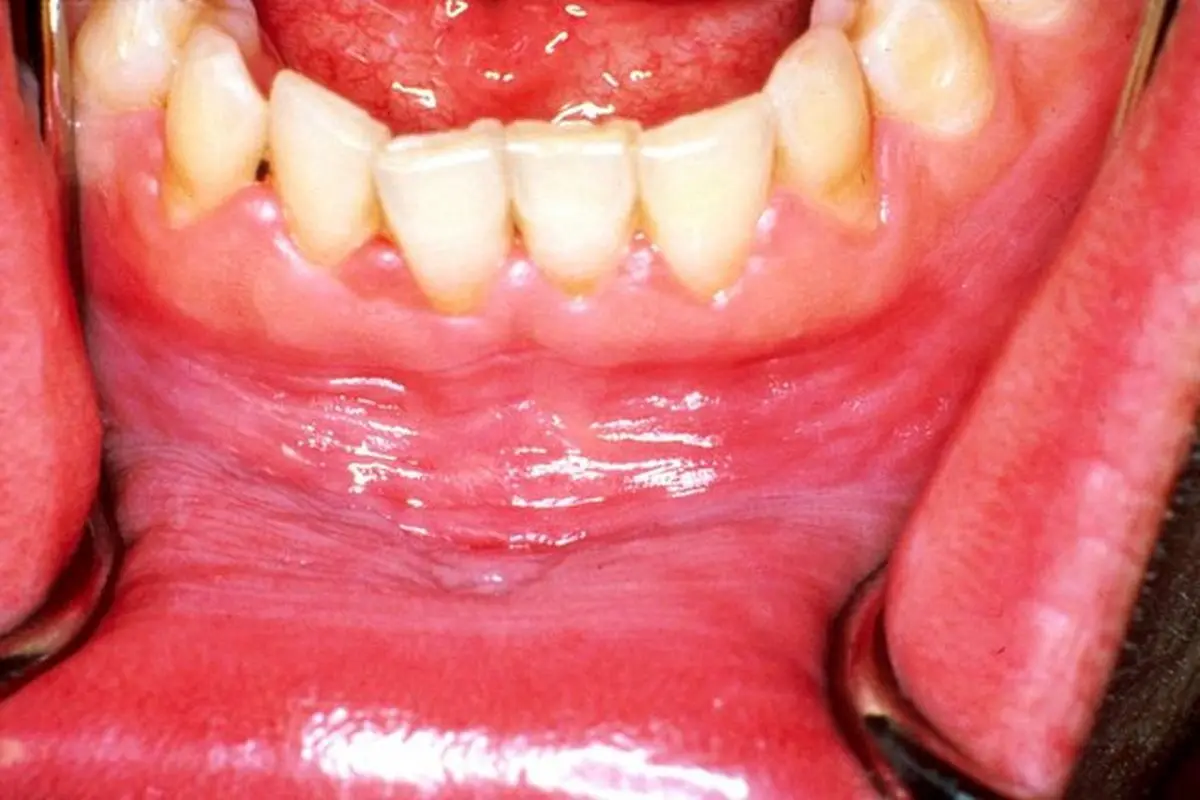

وی افزود: لیکن پلان که یک بیماری پوستی مخاطی مزمن با منشا سیستم ایمنی است، در بیشتر موارد مخاط دهان را مبتلا می‌کند.

محمدی تصریح کرد: ضایعات لیکن پلان دهانی همراه با التهاب است که در این محصول با استفاده از ماده موثره کورکومین که یک ضد التهاب محسوب می‌شود، برای درمان بیماری اقدام می‌شود.

وی افزود: همچنین وجه تمایز این اختراع با سایر درمان‌های این بیماری، مخاط چسب بودن این محصول است؛ چرا که در روش‌های درمانی رایج در حال حاضر پمادهای حاوی کورتن تجویز می‌شود.